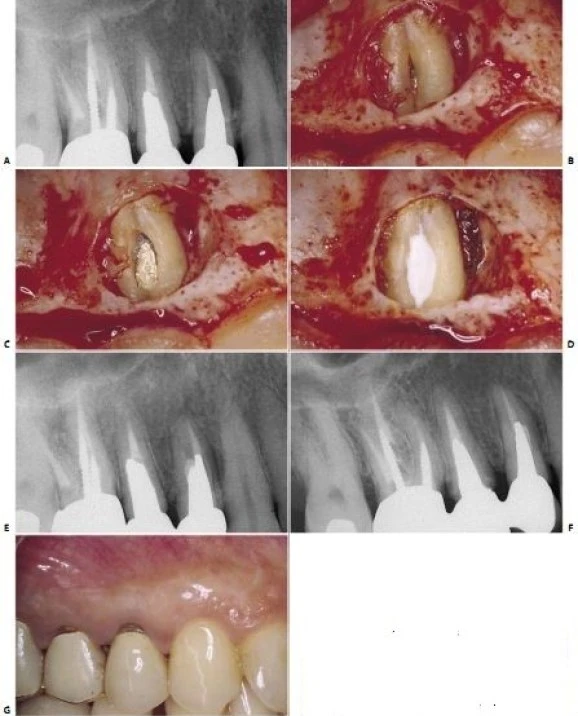

Nếu có sự chia chân phía mặt ngoài- do đó hiển nhiên là có sự hiện diện của hai ống tuỷ mà nhà lâm sàng không chẩn đoán được- thì có thể dẫn đến làm thủng chân răng khi sửa soạn chân răng để đặt chốt hay khi quay cement để gắn chốt (mà nhà lâm sàng cứ nghĩ rằng chỉ có một ống ngoài mà thôi!) (hình 11.48). Vì những lý do trên, nên luôn có quyết định tối ưu số lượng ống tủy cần điều trị, thậm chí nếu chỉ để tự trù thời gian cần cho việc điều trị.

Hình 11.48. Không chẩn đoán thấy sự chia chân và kết quả là làm thủng thành. A. Phim trước điều trị. B. Lật vạt và nhận thấy sự thủng thành. C. Chuẩn bị xoang để hàn chỗ thủng. D. Trám xoang bằng Super EBA. E. Phim sau điều trị. F. Sau hai năm. G. Hình ảnh lâm sàng sau hai năm.